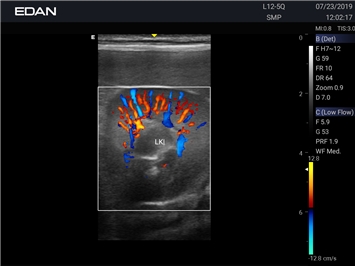

EDAN Acclarix AX2 VET

Ветеринарный ультразвук одним нажатием. Система Acclarix AX2 VET разработана с целью обеспечить бескомпромиссную производительность по доступной цене. Наличие уникальных двойных аккумуляторов в легком корпусе массой 4,5 кг из магниевого сплава позволяет системе Acclarix AX2 VET удовлетворять все потребности ветеринарных исследований, сохранив низкую стоимость.

EDAN Acclarix AX2 VET представляет собой специализированную ветеринарную ультразвуковую систему, сочетающую высокую производительность с доступной ценой. Благодаря продуманной конструкции и передовым технологиям, система обеспечивает качественную диагностику животных различных видов.

Цветовой допплер:

Да